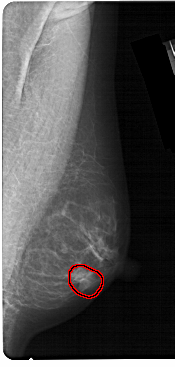

FILE: A_1304_1.RIGHT_MLO.OVERLAY

TOTAL_ABNORMALITIES 1

ABNORMALITY 1

LESION_TYPE MASS SHAPE OVAL MARGINS CIRCUMSCRIBED

ASSESSMENT 4

SUBTLETY 4

PATHOLOGY BENIGN

TOTAL_OUTLINES 1

BOUNDARY